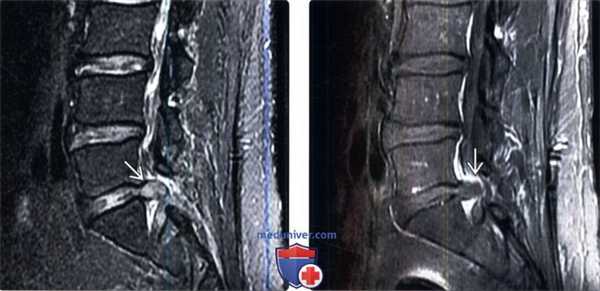

(Слева) Сагиттальный срез, STIR МР-И: пациент после ранее выполненной дискэктомии L5 видна крупная рецидивная грыжа L5-S1, оттесняющая корешок S1. Грыжа отличается четкими границами и несколько гиперинтенсивным сигналом.

(Справа) На сагиттальном Т1-ВИ с КУ у этого же пациента отмечается периферическое контрастное усиление вокруг грыжи за счет накопления контраста в грануляционной ткани и венах эпидурального венозного сплетения, сама грыжа контраст не накапливает.